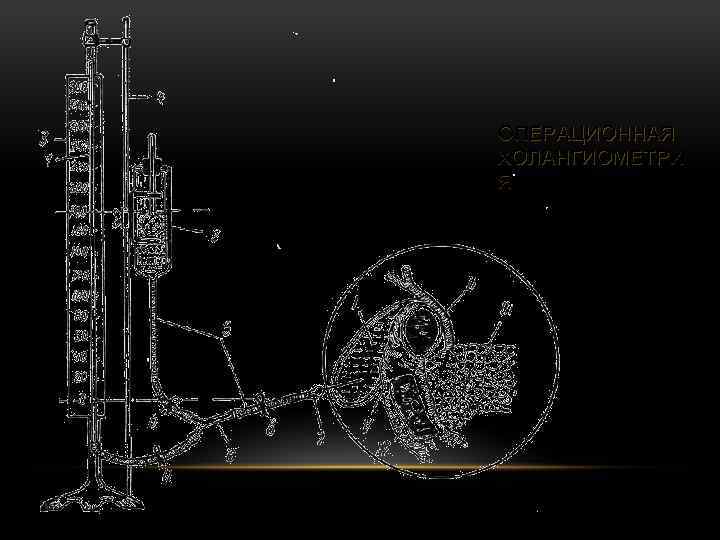

ОПЕРАЦИОННАЯ ХОЛАНГИОМЕТРИ Я

ОПЕРАЦИОННАЯ ХОЛАНГИОМЕТРИ Я